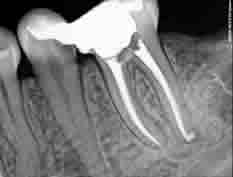

DENTORIUM ordinacije opremljene su sofisticiranim sustavima za tretiranje korijenskog kanala, čišćenje i proširivanje čak i najtanjih kanala koristeći nikal-titan (NiTi) rotirajuće instrumente. Korijenski kanali nerijetko su čitav sustav razgranatih zubnih kanalića koji se šire kao delta rijeke (otuda i ime - root delta). Cijelo to područje treba biti očišćeno i dezinficirano. Neočišćeni ostatak tkiva u kanalu predstavlja područje za razvoj bakterije koje uzrokuju upalu. Zahvaljujući Obtura i Touch'n'Heat toplinsko kondenzacijskim tehnikama punjenja kanala, stomatolozi DENTORIUM ordinacija mogu hermetički ispuniti i najsitnije kanaliće. Zub tretiran na ovakav način služiti će pacijentu mnogo godina, a korijen se može koristiti za buduće složene protetske rekonstrukcije.

Tretmani korjenskih kanala u našim ordinacijama su bezbolni!